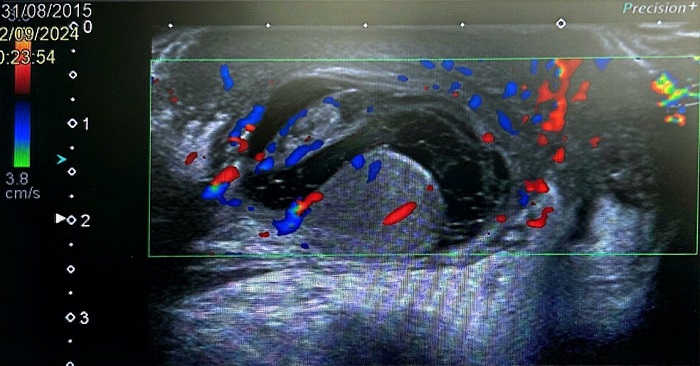

Cinco días después, el paciente regresa por empeoramiento clínico, con incremento del dolor y del edema escrotal, a pesar del tratamiento. En la nueva exploración física se aprecia aumento del volumen escrotal, eritema marcado, sensibilidad a la palpación y endurecimiento del hemiescroto derecho. El reflejo cremastérico se mantiene presente, pero el signo de Prehn es ahora negativo. Se realiza una nueva ecografía escrotal que identifica una colección líquida multitabicada y heterogénea alrededor del testículo derecho, sugestiva de hidrocele complicado por piocele (Figura 1). El urocultivo recogido en la visita previa a urgencias continúa siendo negativo.

| Figura 1. Ecografía testicular del paciente, que muestra una colección tabicada compatible con piocele |